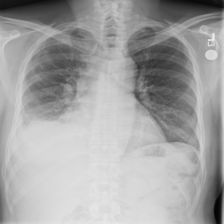

4.5 Chest X-Ray Dataset

Motivation. Chest X-ray imaging is a common procedure for diagnosing conditions such as atelectasis, cardiomegaly, and effusion, among others. Although radiologists are skilled at analyzing such images, modern machine learning models are increasingly competitive in diagnostic performance \citepahmad2021reviewing. Therefore, ML models may prove useful in assisting radiologists in making diagnoses. However, in the absence of an explanation, radiologists may only trust the model output if it matches their own predictions. Moreover, inaccurate AI assistants are shown to negatively affect diagnostic performance \citepyu2024heterogeneity. To address this problem, explainability could be employed as a safeguard to help radiologists decide whether or not to trust the model. As such, it is important for machine learning models to provide explanations for their diagnoses.

Problem Setup. We use the NIH-Google dataset \citepmajkowska2020chest available from the TorchXRayVision library \citepcohen2022xrv. This is a relabeling of the NIH ChestX-ray14 dataset \citepwang2017chestx which improved the quality of the original labels. It contains 28,868 chest X-ray images labeled for 14 common pathology categories: atelectasis, calcification, cardiomegaly, etc. We randomly partition the dataset into train/test splits of 23,094 and 5,774, respectively. The task is a multi-label classification problem for identifying the presence of each pathology.

Expert Features. Radiology reports commonly refer to anatomical structures (e.g., spine, lungs), which allows radiologists to perform and communicate accurate diagnoses to patients. We provide these expert-interpretable features in the form of anatomical structure segmentations. However, because we could not find datasets with both pathology labels and anatomical segmentations, we used a pre-trained model from TorchXRayVision to generate the structure labelings for each image. We use explicit expert alignment as described in Equation 2 to compute alignment of an extracted feature and the 14 predicted anatomical structure segments, including the left clavicle, heart, etc. Details of the Chest X-Ray dataset can be found in Appendix A.5.

(a) Full image

(b) Right lung

(c) Left lung